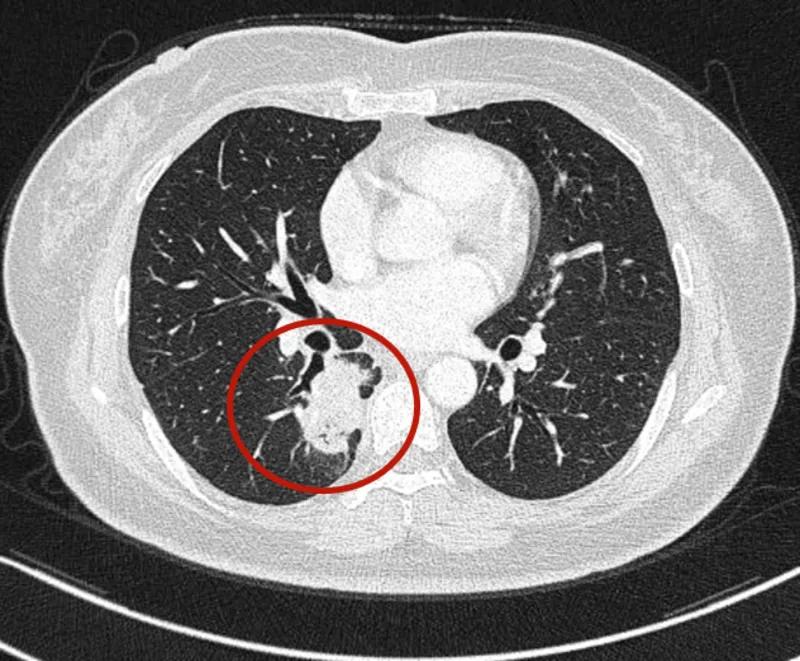

可见是右下肺达近5厘米的肿块,并上叶磨玻璃结节以及斜裂、水平裂多发微小结节。影像是如何的呢?

到底该如何考虑?下一步该如何决策?我的意见是:右下叶红色圈起来的考虑是肺癌,浸润性腺癌可能性大;右上叶磨玻璃结节粉色圈起来的考虑原位癌或不典型增生可能性大;绿色圈起来的基本上是叶裂处,从密度来看更像良性,但因为有右下叶的病灶在,也可能是种植转移,但术前较难确定。PET-CT可以考虑,但也有假阴性或假阳性。个人意见是如果没有远处其他确切转移,建议胸腔镜下探查,如果微小实性结节非转移性,则右下肺癌仍能手术的。如果真若是转移,也可取行病理依据,并送基因检测与免疫组化等检查,而单孔胸腔镜下探查下创伤小,恢复快,当然若不是转移,顺便镜下行右下叶切除并清扫淋巴结就行。